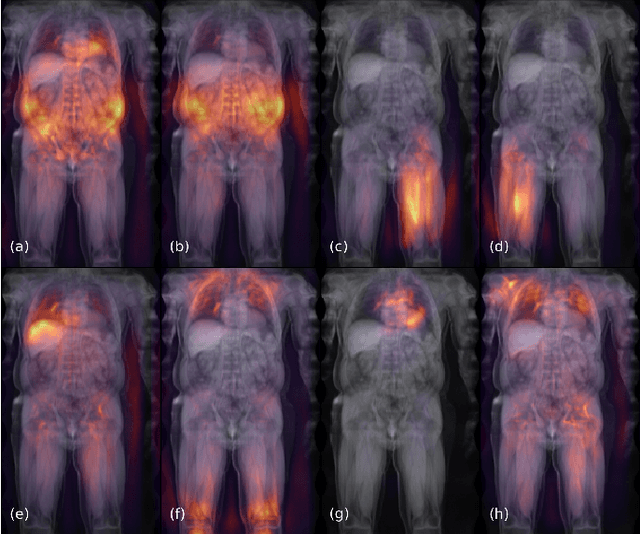

Abstract:UK Biobank (UKB) is conducting a large-scale study of more than half a million volunteers, collecting health-related information on genetics, lifestyle, blood biochemistry, and more. Medical imaging furthermore targets 100,000 subjects, with 70,000 follow-up sessions, enabling measurements of organs, muscle, and body composition. With up to 170,000 mounting MR images, various methodologies are accordingly engaged in large-scale image analysis. This work presents an experimental inference engine that can automatically predict a comprehensive profile of subject metadata from UKB neck-to-knee body MRI. In cross-validation, it accurately inferred baseline characteristics such as age, height, weight, and sex, but also emulated measurements of body composition by DXA, organ volumes, and abstract properties like grip strength, pulse rate, and type 2 diabetic status (AUC: 0.866). The proposed system can automatically analyze thousands of subjects within hours and provide individual confidence intervals. The underlying methodology is based on convolutional neural networks for image-based mean-variance regression on two-dimensional representations of the MRI data. This work aims to make the proposed system available for free to researchers, who can use it to obtain fast and fully-automated estimates of 72 different measurements immediately upon release of new UK Biobank image data.

Abstract:Large-scale medical studies such as the UK Biobank examine thousands of volunteer participants with medical imaging techniques. Combined with the vast amount of collected metadata, anatomical information from these images has the potential for medical analyses at unprecedented scale. However, their evaluation often requires manual input and long processing times, limiting the amount of reference values for biomarkers and other measurements available for research. Recent approaches with convolutional neural networks for regression can perform these evaluations automatically. On magnetic resonance imaging (MRI) data of more than 40,000 UK Biobank subjects, these systems can estimate human age, body composition and more. This style of analysis is almost entirely data-driven and no manual intervention or guidance with manually segmented ground truth images is required. The networks often closely emulate the reference method that provided their training data and can reach levels of agreement comparable to the expected variability between established medical gold standard techniques. The risk of silent failure can be individually quantified by predictive uncertainty obtained from a mean-variance criterion and ensembling. Saliency analysis furthermore enables an interpretation of the underlying relevant image features and showed that the networks learned to correctly target specific organs, limbs, and regions of interest.

Abstract:Objective: Automated analysis of MRI with deep regression has the potential to provide medical research with a wide range of biological metrics, inferred at high speed and accuracy. Methods: The UK Biobank study has successfully imaged more than 32,000 volunteer participants with neck-to-knee body MRI. Each scan is linked to extensive metadata, providing a comprehensive survey of imaged anatomy and related health states. Despite its potential for research, this vast amount of data presents a challenge to established methods of evaluation, which often rely on manual input. In this work, neural networks were trained for regression to infer various biological metrics from the neck-to-knee body MRI automatically, with a ResNet50 in 7-fold cross-validation. No manual intervention or ground truth segmentations are required for training. The examined fields span 64 variables derived from anthropometric measurements, dual-energy X-ray absorptiometry (DXA), atlas-based segmentations, and dedicated liver scans. Results: The standardized framework achieved a close fit to the target values (median R^2 > 0.97). Interpretation of aggregated saliency maps indicates that the network correctly targets specific body regions and limbs, and learned to emulate different modalities. On several body composition metrics, the quality of the predictions is within the range of variability observed between established gold standard techniques. Conclusion and Significance: The deep regression framework robustly inferred a wide range of medically relevant metrics from the image data. In practice, this technique could provide accurate, image-based measurements for medical research months or years before the more established reference methods have been fully applied.